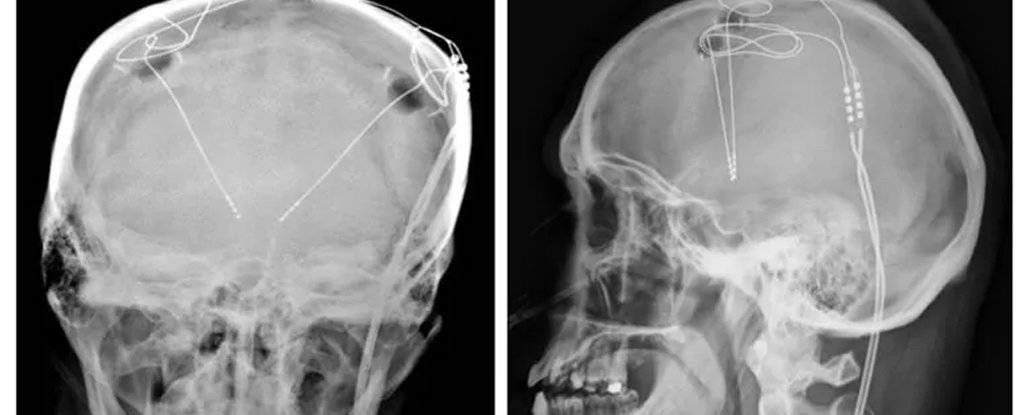

Речь идет о специальных электродах глубинного стимулятора мозга. Устройство способно воздействовать непосредственно на зоны мозга, корректируя привычки и поведение.

«В результате операции, которая длилась семь часов, врачам удалось имплантировать электроды в нужные зоны головного мозга. Врачи надеются, что, посылая импульсный ток через электроды, они смогут регулировать дисбаланс в схемах вознаграждения пациента», – сообщает издание.